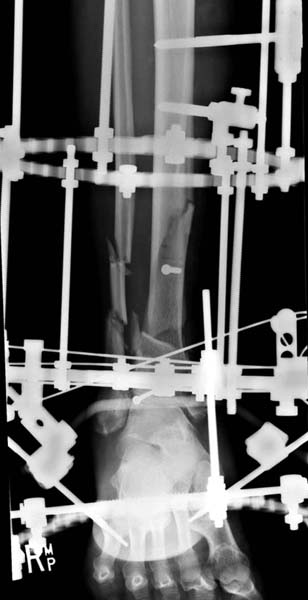

Современную тактику лечения переломов пилона описали коллеги, а мне остается подтвердить клинически. В многоэтапном лечении главное - это предупреждение сокращения мягких тканей, от которого зависит судьба конечности. Дистракция любым наружным фиксатором, и по готовности мягких тканей - премежуточная или окончательная фиксация.

В нашем случае, травма в результате коллапса крыши. Открытый перелом. Ургентные Irrigation and Debridment, дистракция наружным фиксатором. В госпиталях первого уровня редко бывает изолированная травма, и на другой стороне повреждение стопы с переломом навикулярной кости. После обработки раны - вакуум и двухсторонние наружные фиксаторы.

После спадения отека вариантов фиксации много, включая мининвазивную технику, но данный случай закончили установкой простого аппарата Илизарова.